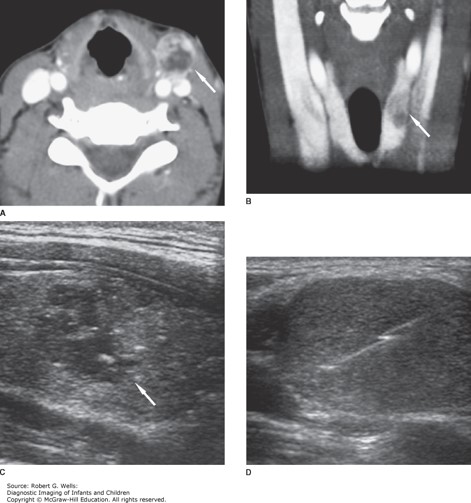

Differentiated thyroid carcinoma (papillary). This 14-year-old girl presented with a palbable left neck mass. A. Axial contrast-enhanced CT at the level of the mass shows an enlarged, heterogeneously enhancing lymph node (arrow). B. The primary tumor is visible on this coronal image as a hypoattenuating lesion (arrow) in the left lobe of the thyroid. C. The nodule (arrow) is predominantly hypoechoic on this longitudinal sonographic image. D. Percutaneous core needle biopsy of the metastatic lymph node provided material for a histological diagnosis.

The correct answer is “C.” The most common presentation of a patient with thyroid cancer is the presence of a solitary thyroid nodule or mass. Although approximately 2% of children have palpable thyroid nodules, most of these are benign adenomas or cystic lesions. Patients with thyroid cancer may have a history of external radiation to the head and neck, exposure to nuclear fallout, a history of rapid growth of the thyroid nodule, a firm or fixed neck mass, hoarseness, dysphagia, or cervical lymphadenopathy. Thyroid cancer is divided into four main types: papillary, follicular, medullary, and anaplastic. In children, the vast majority of masses are differentiated thyroid cancer, which includes both papillary and follicular thyroid carcinomas. Medullary thyroid carcinoma (MTC) is notable due to the production of calcitonin from the parafollicular or C cells of the thyroid gland, and it may be associated with multiple endocrine neoplasia type 2A (MEN 2A) or MEN 2B. Diagnosis of thyroid carcinoma is made by fine needle aspiration biopsy.